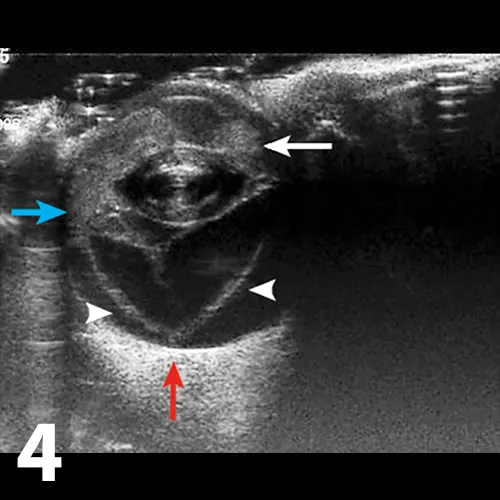

Figure 4

Ultrasonographic image of an eye, with the cornea oriented to the top of the image. The anterior chamber is filled with hyperechoic material, consistent with hemorrhage and fibrin (white arrow) that were evident on examination. The retina is detached (arrowheads) and is forming the classic seagull sign; 2 hyperechoic linear structures representing the retina (arrowheads) within the vitreal chamber, attached at the ora ciliaris retinae (blue arrow) and the optic nerve (red arrow).

Ocular ultrasonography is necessary if the posterior segment of the eye cannot be visualized because of corneal opacity, debris in the anterior chamber associated with uveitis, or cataract; ultrasonography may show a thin, linear hyperechoic structure protruding into the vitreal chamber. Most commonly, the retina will remain attached at the optic nerve and ora ciliaris retinae, which is where the ciliary body transitions into choroid and the peripheral retina begins (Figure 4). This will cause a gullwing appearance, or “seagull” sign, on ultrasonography, but partial detachments or disinsertions (tearing of the retina in addition to detachment) will not show the classic seagull sign.